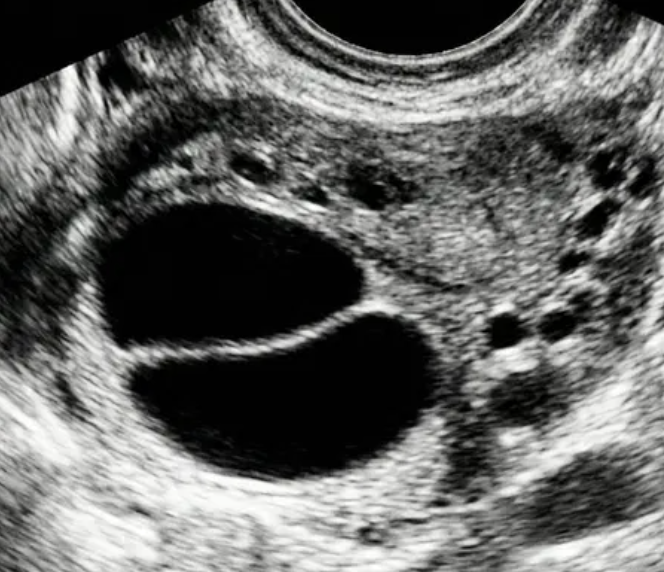

Risco: <1%Cistos simples, uniloculares lisos, lesões benignas clássicas (hemorrágico, dermoide, endometrioma, paraovariano, peritoneal, hidrossalpinge).

O-RADS US 3 — Baixo Risco de Malignidade

Risco: <10%Cisto unilocular ≥ 10 cm, cistos dermoides/endometriomas/hemorrágicos ≥ 10 cm, cisto unilocular com parede irregular < 3 mm, cisto multilocular < 10 cm com parede lisa, lesão sólida com superfície lisa.